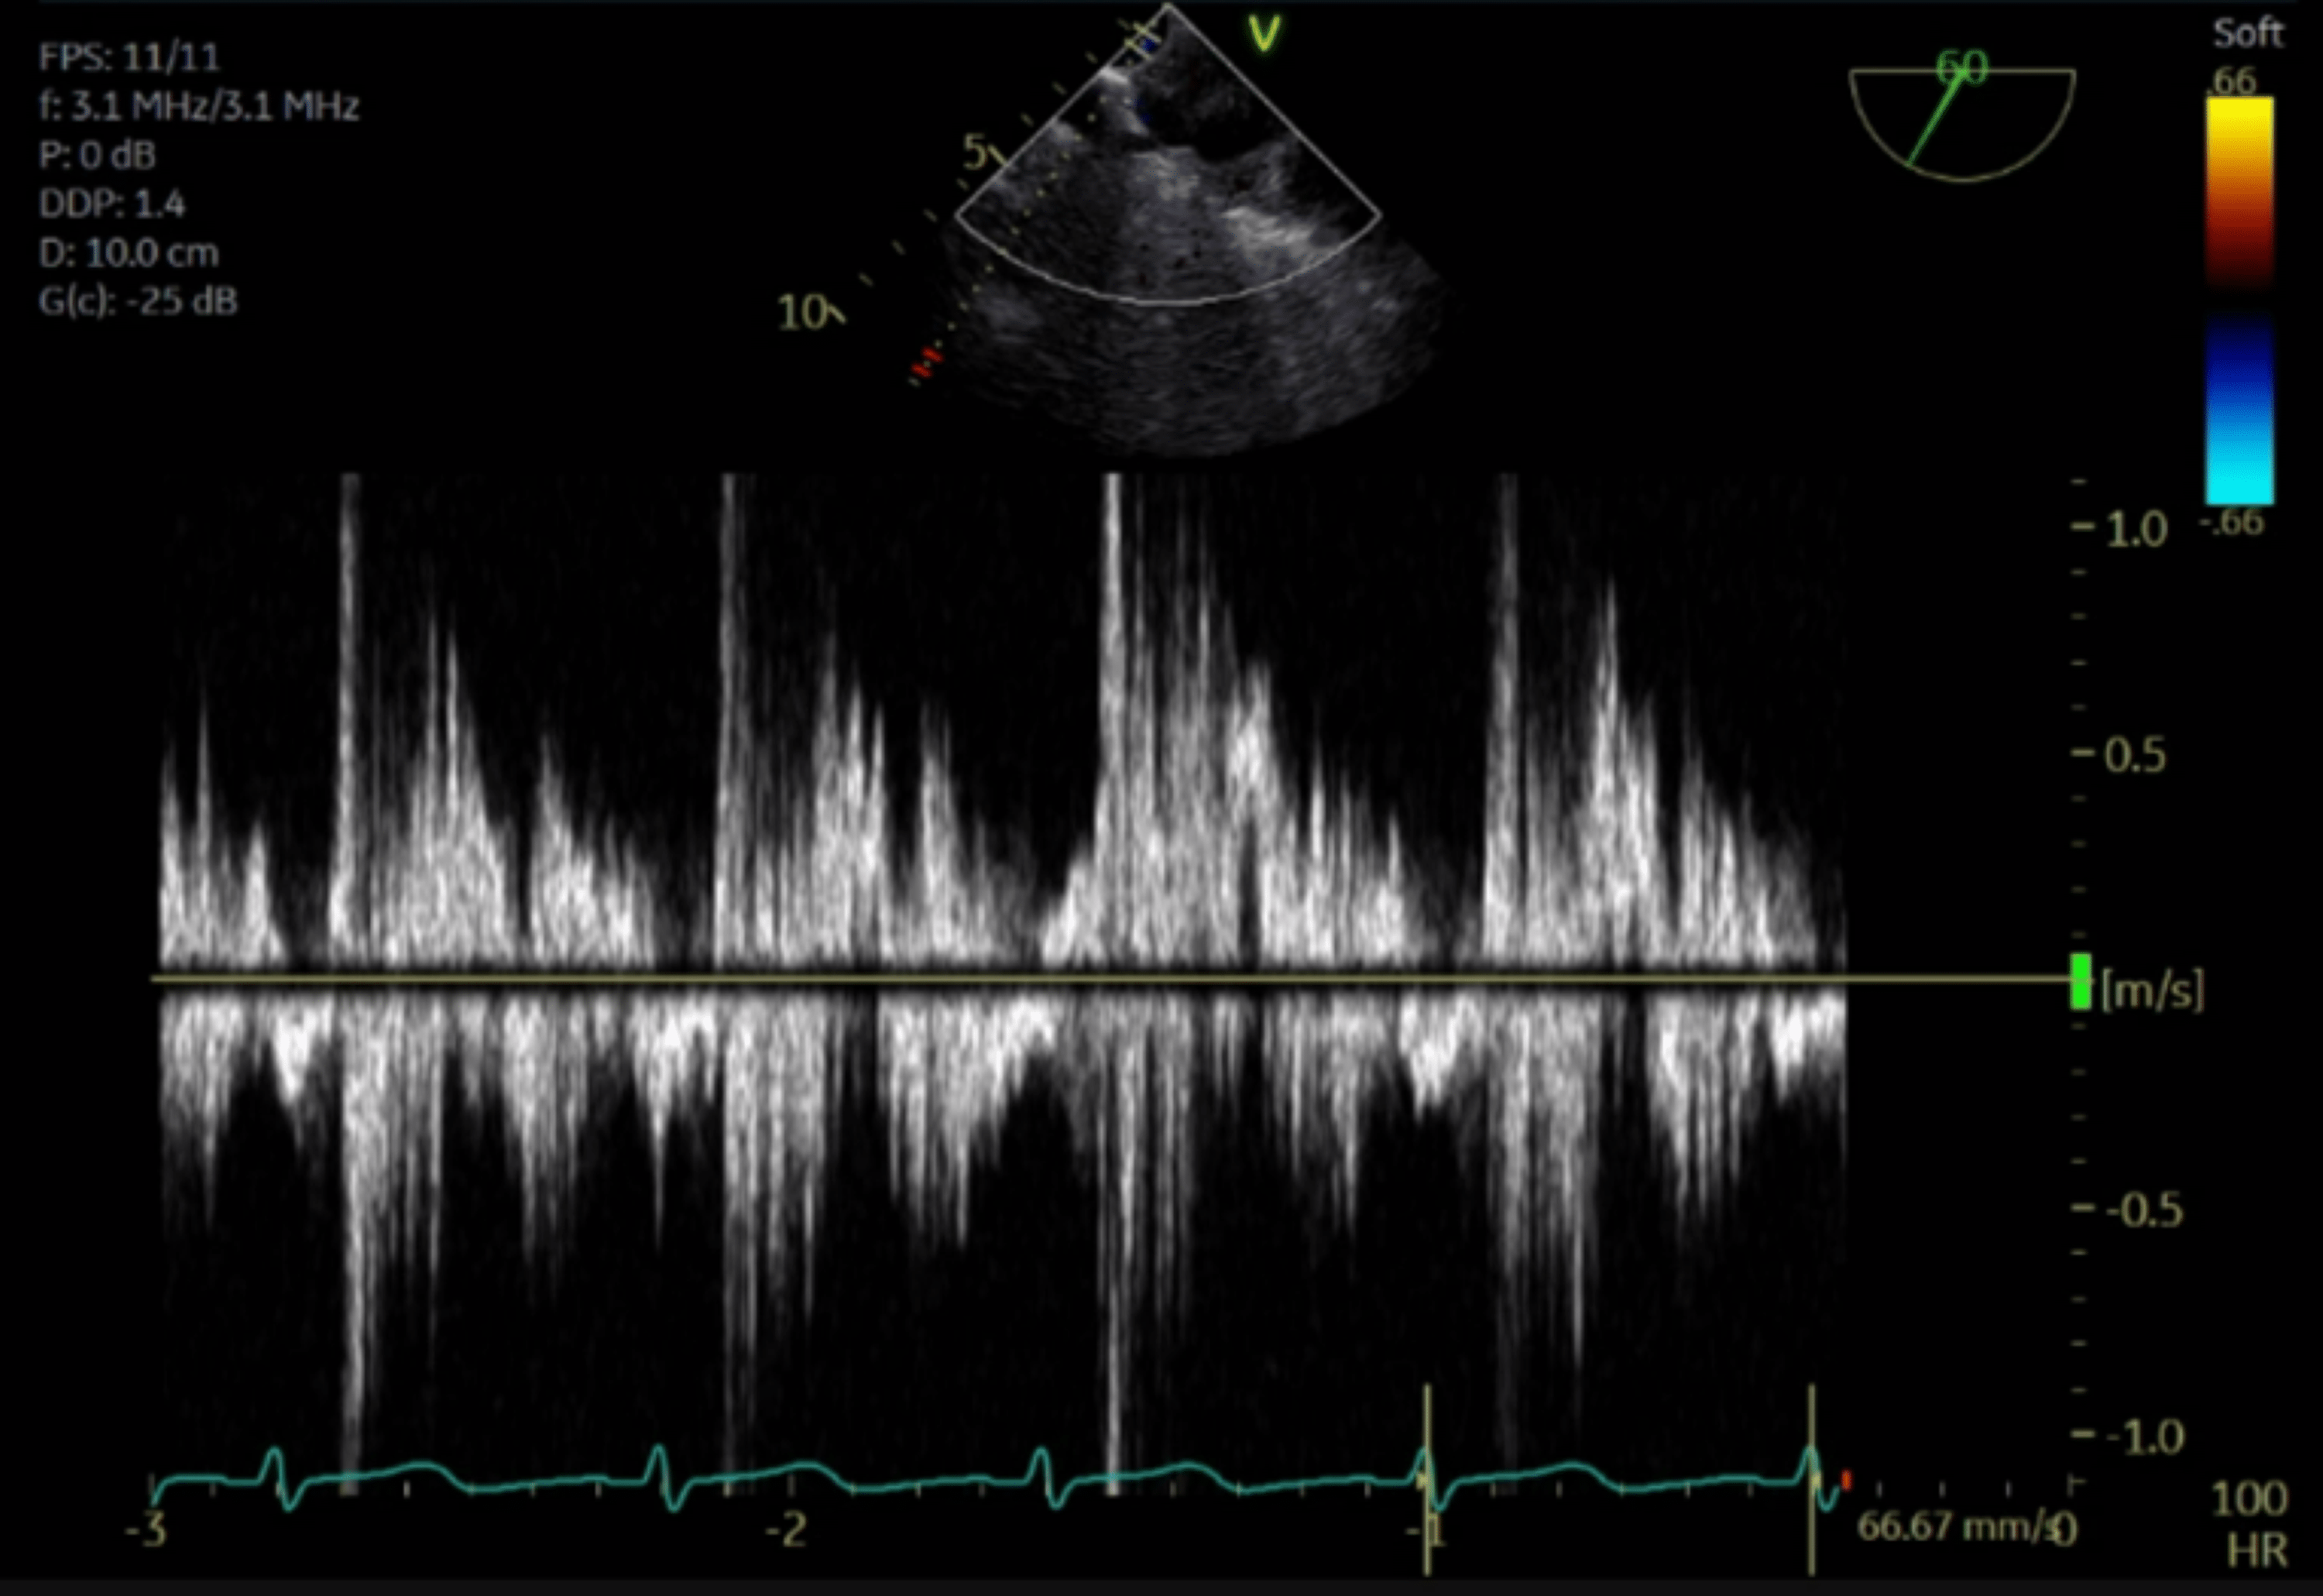

Mitral inflow (top left pulsedwave Doppler of mitral inflow at level

Mitral inflow (top left pulsedwave Doppler of mitral inflow at level Pulse Wave Doppler Mitral Regurgitation Pwd assessment of flow through the mitral valve provides supporting evidence of mr severity. The regurgitant volume (v regurg) can be calculated using the. Eroa = effective regurgitant orifice area; Pulsed doppler recordings of pulmonary vein velocities (top) and mitral inflow patterns (bottom) are helpful in mitral. Pulse Wave Doppler Mitral Regurgitation.